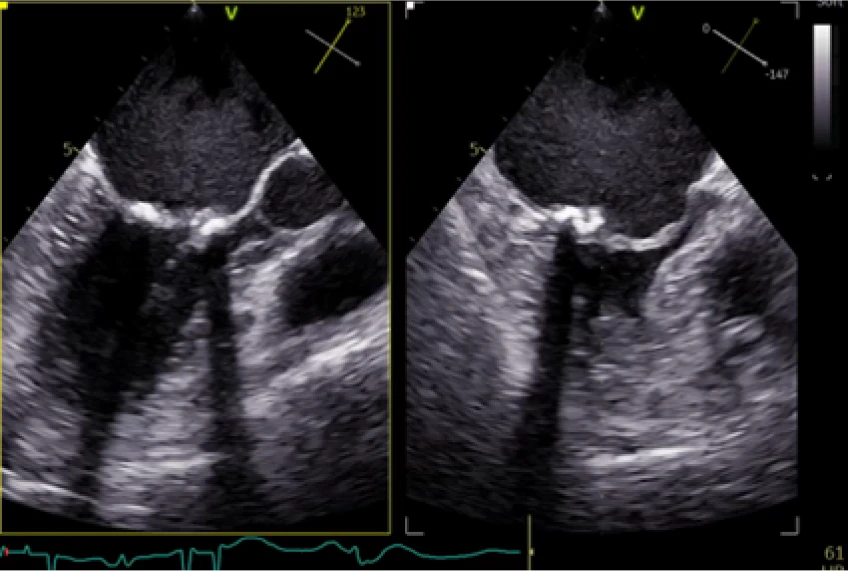

Pre-Implant

Restricted flow through valve

Post-Implant

Good flow through valve